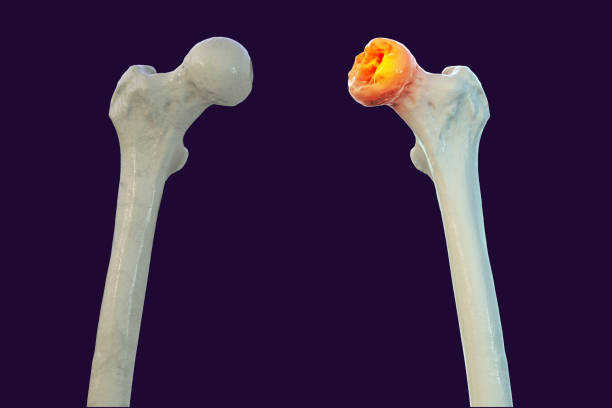

Interruption de la vascularisation de la tête fémorale conduisant à sa nécrose osseuse. Peut survenir après traumatisme, corticothérapie prolongée ou alcoolisme chronique.

Vissage, ostéotomie, ou PTH selon le stade